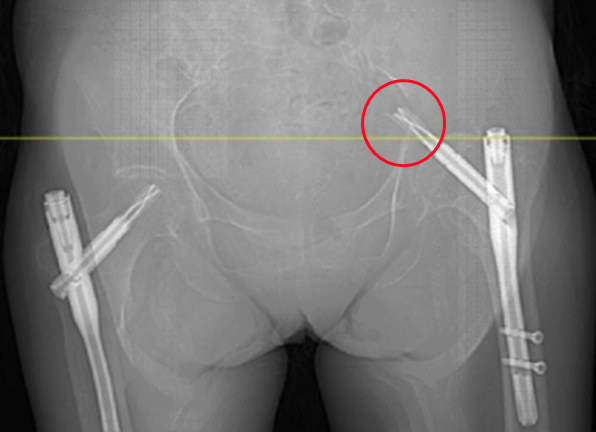

"老人骨质疏松严重,又有低血糖、心脏问题,千万小心再次跌倒!"出院时医生的叮嘱言犹在耳。然而7月的一天,邱婆婆再次摔倒——这次是右侧髋部着地,剧痛让她瞬间无法站立。更糟的是,检查发现不仅骨盆骨折,此前植入的固定钢钉竟因冲击力穿破股骨头刺入盆腔!

"情况比想象中凶险得多。"主刀医生尹一然教授解释,这枚"跑偏"的钢钉紧邻大血管,稍有不慎就会引发大出血;而老人除了高龄,还合并骨质疏松、重度贫血、肾功能不全、心脏问题等16种基础疾病,手术风险极高。

8月8日,一场精密的"生命保卫战"打响。由骨科尹一然教授领衔,联合麻醉科、心血管内科、肾内科等专家制定方案:既要取出刺入盆腔的钢钉,又要解决髋臼缺损和骨量流失难题,还要确保新关节稳固。

先小心翼翼取出嵌在盆腔的钢钉,避免损伤血管;